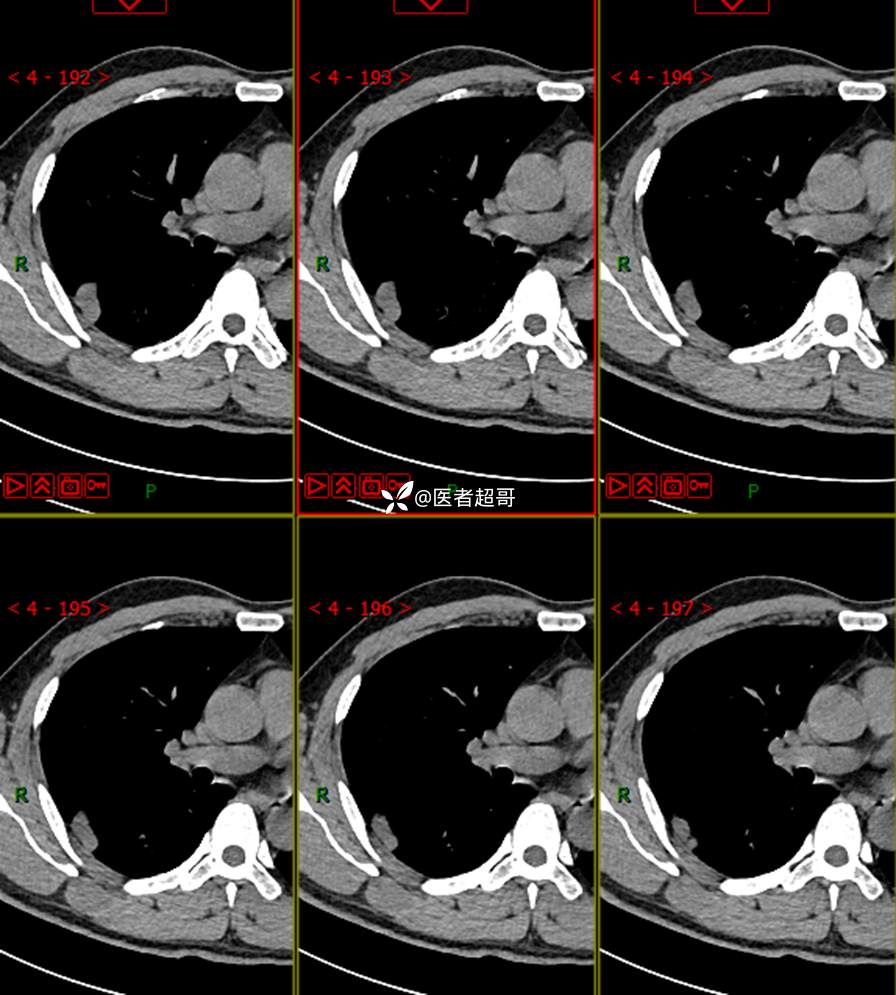

现病史:患者1年余前于体健中心行胸部X片发现右上肺叶密度增高影,无明显咳嗽,咳痰,无痰中带血及咯血,无胸痛及胸闷、气短,无发热、盗汗及全身乏力。无头痛、头晕,无腹痛、腹胀及恶心、呕吐,无声音嘶哑及呛咳,未行特殊治疗。后患者定期复查胸部CT,未见明显变化。2023-2-6患者于我院复查胸部CT:右肺上叶、下叶交接处胸膜下见实性结节影,最大截面约2.6cm×1.4cm,较前增大,建议行手术治疗。今为求进一步诊治,遂来我院就诊,门诊以“肺肿物”收入我院,患者自发病以来,神志清,精神可,饮食可,睡眠良好,大小便正常,近期体重未见明显增减。